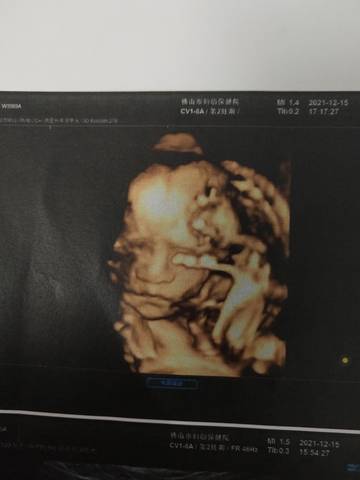

你们觉得男宝宝几率大还是女宝宝几率大

journal_insert_pic_1681149393journal_insert_pic_1681149417journal_insert_pic_1681149445journal_insert_pic_1681149469

你好。我们是判断不了男宝宝跟女宝宝的,孕期定期检查,我觉得宝宝健康就好的。祝心想事成 。

男宝宝的机率大

你好亲爱的,通过这个来判断男孩女孩是不太准确的哈。那么这个男孩女孩都是我们最爱的宝贝哈,我们要给他同等的关爱和呵护,也祝你可以如愿以偿,心想事成,祝你好运。

女

男孩子吧!